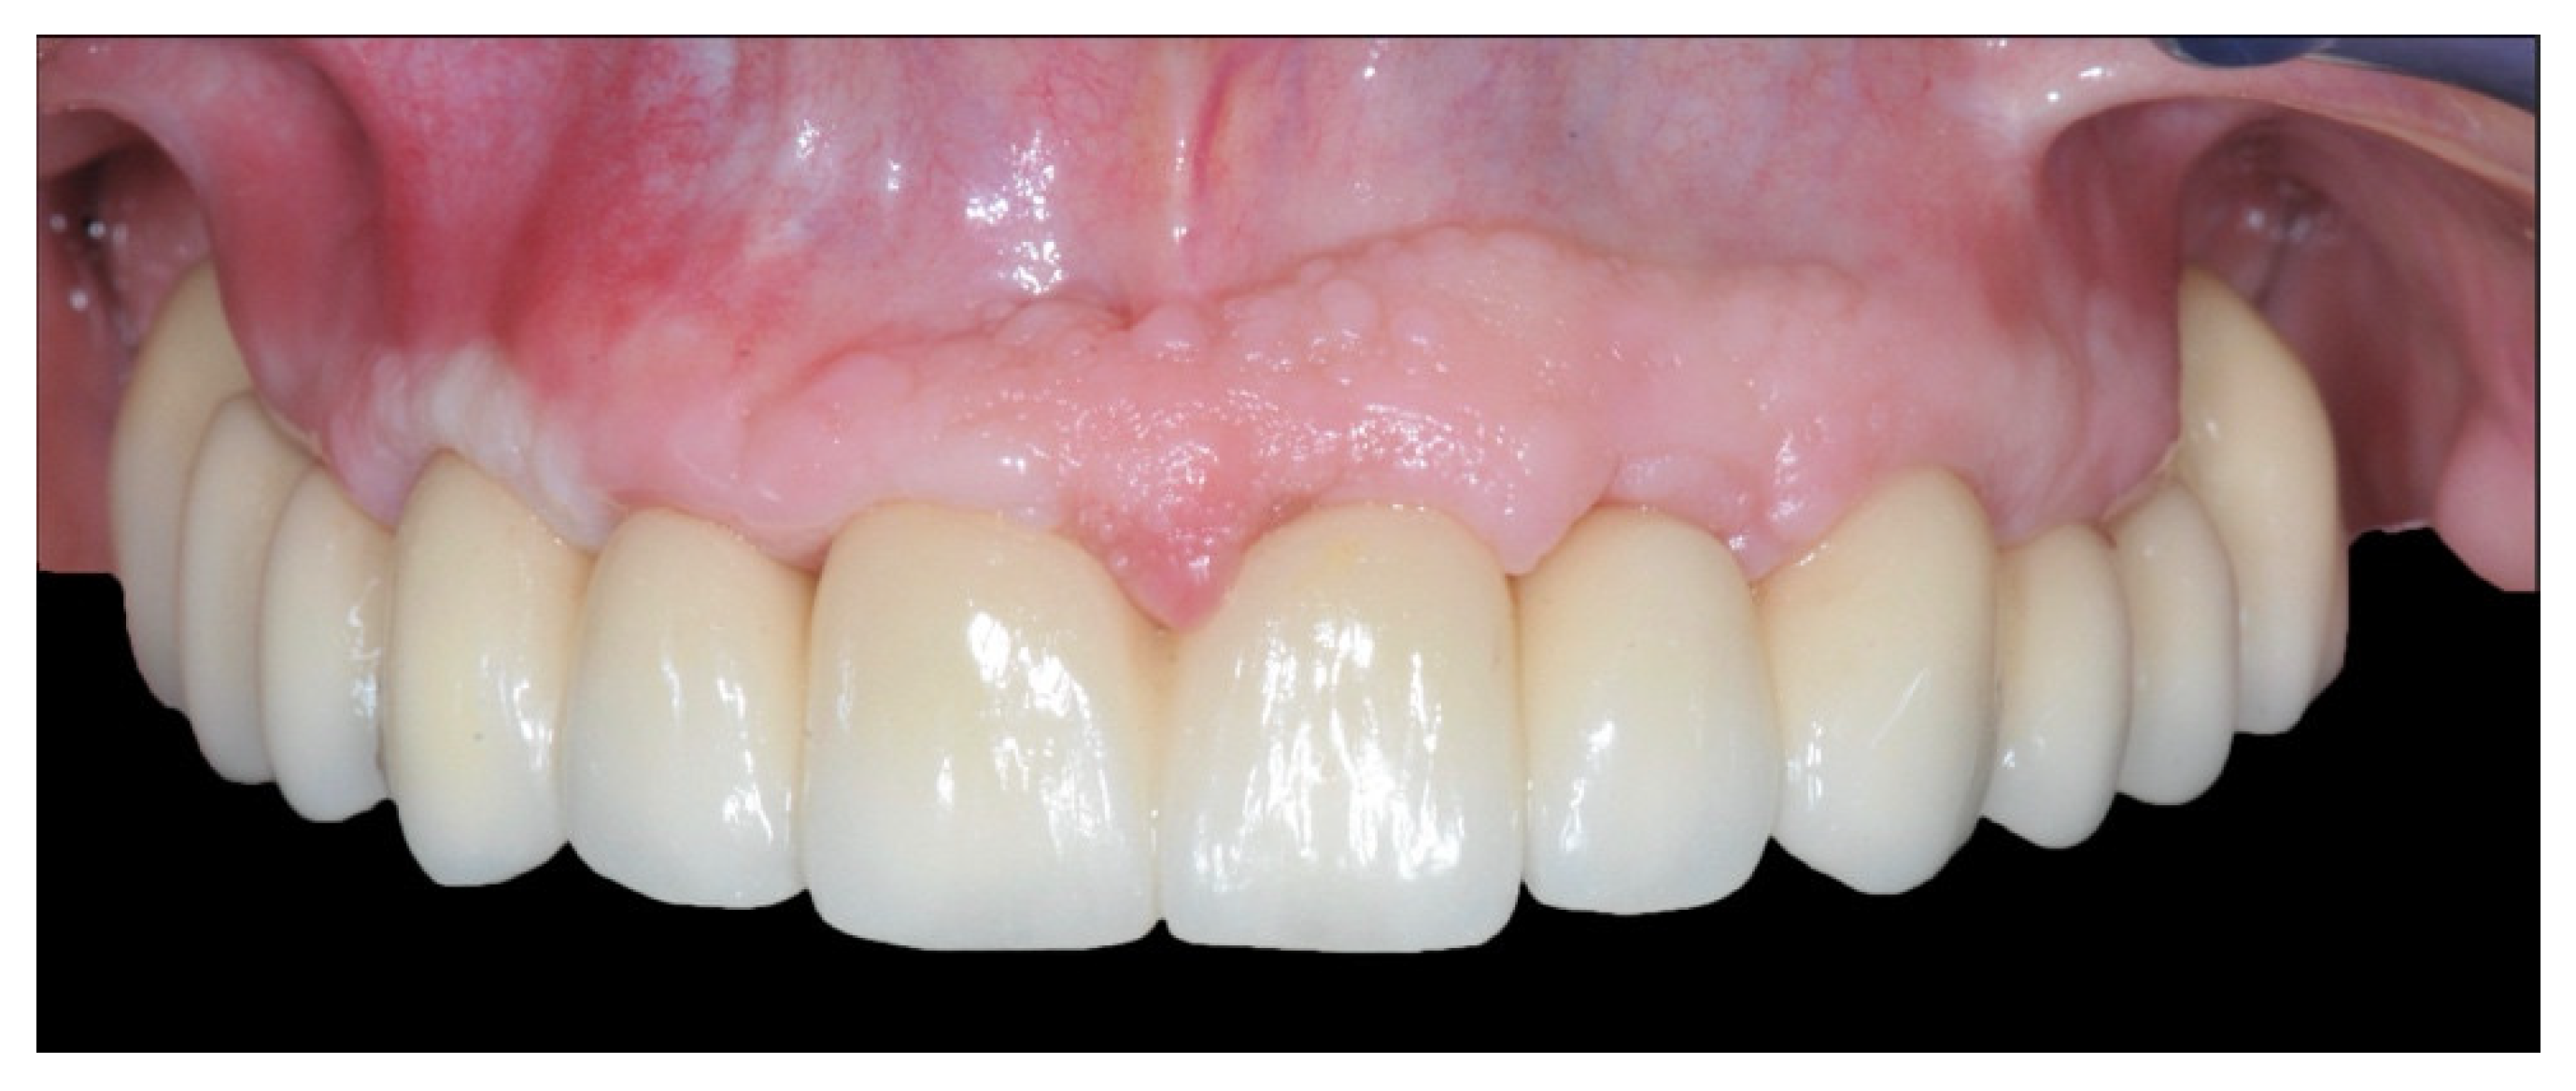

Full Digital Model-Free Maxillary Prosthetic Rehabilitation by Means of One-Piece Implants: A Proof of Concept Clinical Report with Three-Years Follow Up